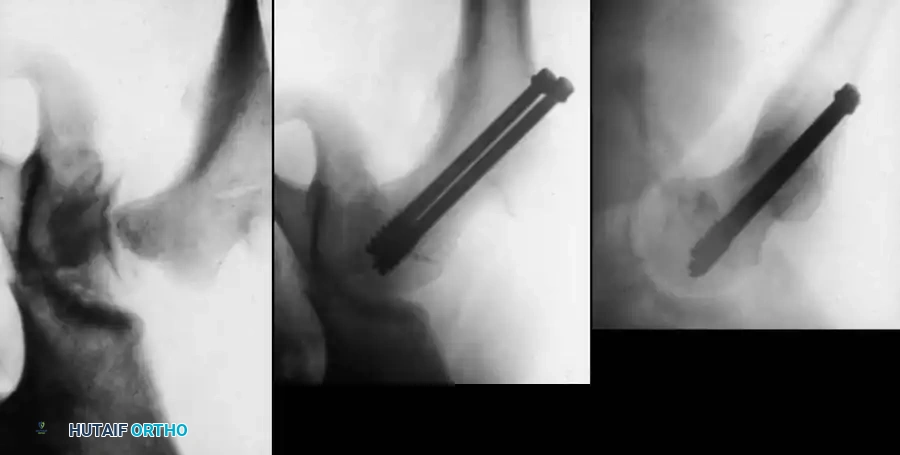

Fig. 11: Transcervical fracture stabilized with cannulated screws stopping short of the capital femoral physis.

Fig. 12: Lateral fluoroscopic view confirming central placement of the screws within the femoral neck.

- Fixation:

- Use two or three partially threaded cannulated screws (typically 4.5 mm or 6.5 mm depending on the child's size).

- Crucial Step: The pediatric femoral neck is extremely hard. You must overdrill the near cortex to achieve a lag effect and prevent fracture distraction.

- Stop the threads short of the physis to prevent growth arrest. Do not use adult triflanged nails, as the impaction force will distract the fracture or separate the physis.